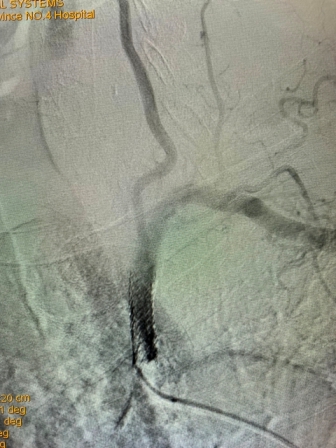

2021年8月5日,21点策略指南站 神经内科神经介入专家团队成功完成首例锁骨下动脉再通介入术

(术前造影) (术后再通造影)